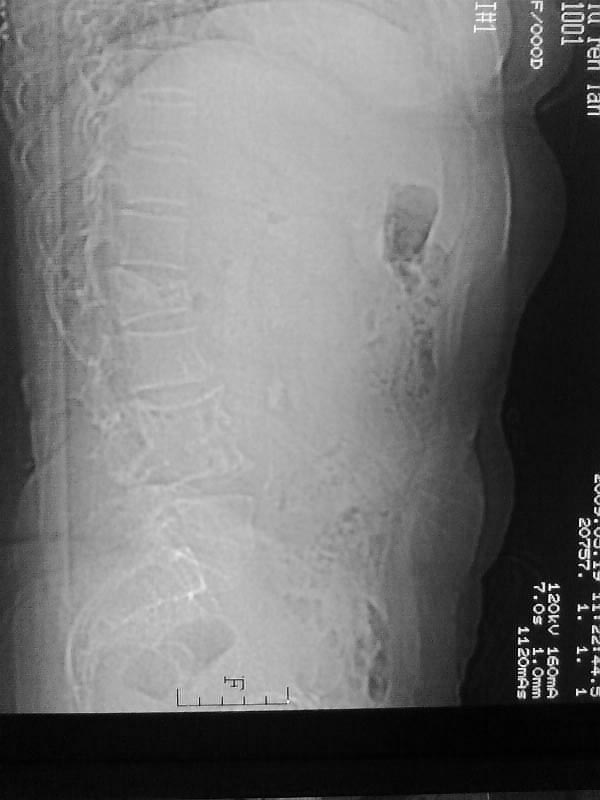

定位相示l2呈楔形改变(ct示陈旧性骨折改变,图像未传),l4.5椎体融合,以下是l4.5ct平扫.请各位看看,

定位像咋看也是腰一压缩性骨折,因为它上面的一个椎体的肋骨。

1、l1压缩性骨折(陈旧性)。

就是腰1压缩性骨折,腰3\\4椎体结核(融合),水平骶椎.

是l1压缩,不是l2写错了

支持 l1椎体陈旧性压缩性骨折;l3、4椎体结核(融合);水平骶椎。